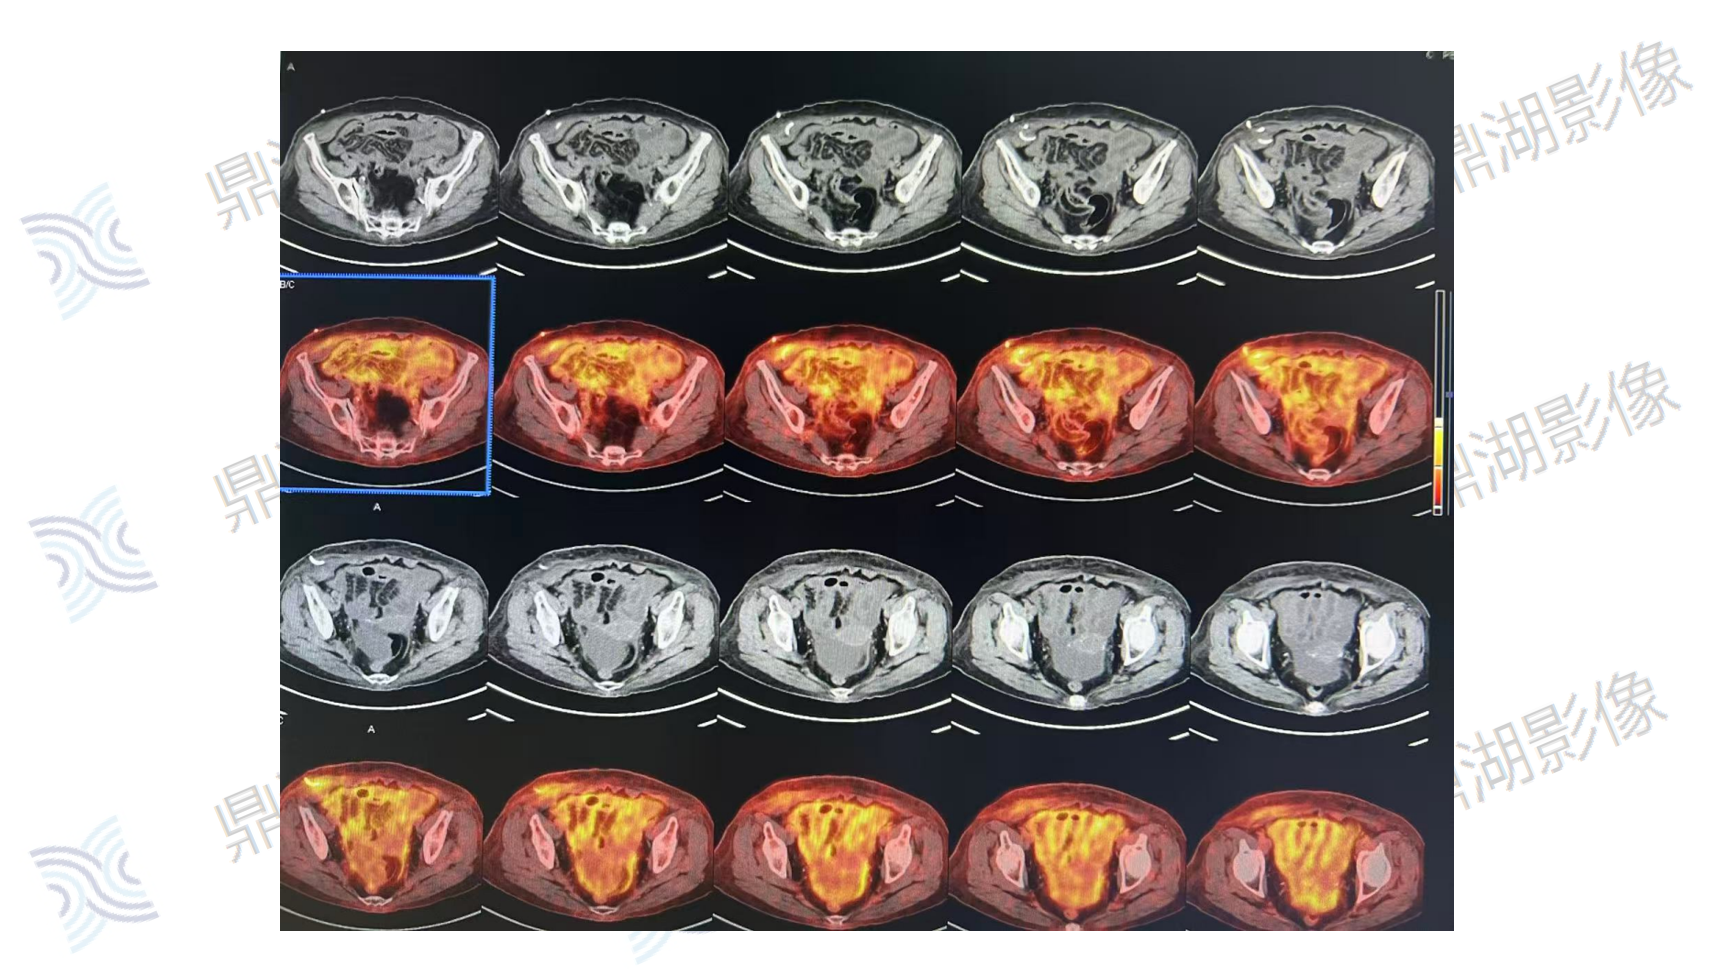

腹部上皮样间皮瘤

主诉:腹痛10天,CT检查示腹膜结节及肿块,腹腔积液;血红蛋白减低